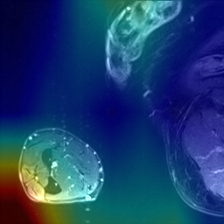

To evaluate model interpretability via DS and DSc\mathrm{DS}_{c}roman_DS start_POSTSUBSCRIPT italic_c end_POSTSUBSCRIPT, we apply both MoRF and LeRF occlusion strategies. In the MoRF strategy, we iteratively apply a Gaussian blur to the image regions deemed most salient by the interpretability method, progressively attenuating their visual information. Conversely, the LeRF strategy blurs the least salient regions first. An illustration of the MoRF process is shown in Figure 5. This figure presents a step-by-step example to clarify the procedure: starting with the original saliency map, we progressively blur the top 10% of pixels deemed most important by the model. This deletion continues in increments, such that by the 80% step, the majority of less relevant pixels are blurred, ultimately reaching 100% occlusion of the image. By measuring the change in the model’s prediction probability as each block of pixels is blurred, we compute DS and DSc\mathrm{DS}_{c}roman_DS start_POSTSUBSCRIPT italic_c end_POSTSUBSCRIPT as the area between the model’s output curves under the MoRF and LeRF interventions.

Refer to caption

(a) Original Image

(b) Interpretation

(c) 10% Blur

(d) 80% Blur

Figure 5: Progressive blurring of the image based on MoRF strategy.